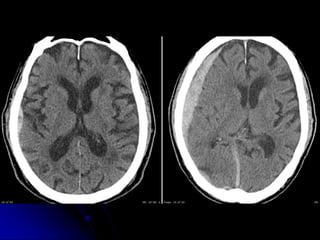

INCIDENTAL

FINDINGS &

COMORBIDITIES